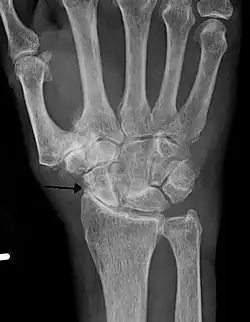

-

Severe osteoarthritis and osteopenia of the carpal joint and 1st carpometacarpal joint -

Diagnosis is made with reasonable certainty based on history and clinical examination.[52][53] X-rays may confirm the diagnosis. The typical changes seen on X-ray include: joint space narrowing, subchondral sclerosis (increased bone formation around the joint), subchondral cyst formation, and osteophytes.[54] Plain films may not correlate with the findings on physical examination or with the degree of pain.[55]